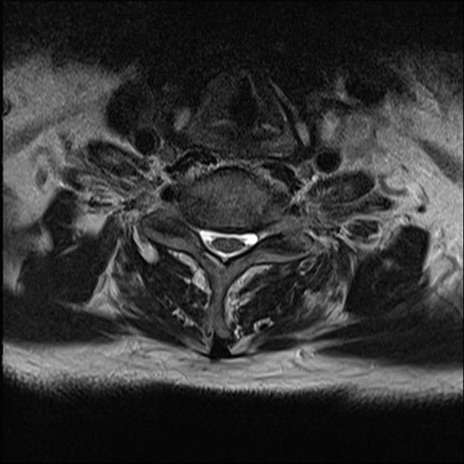

【整形】TIPS症例7 頚椎MRI T2WI(横断像)

頚椎MRI

矢状断像と横断像